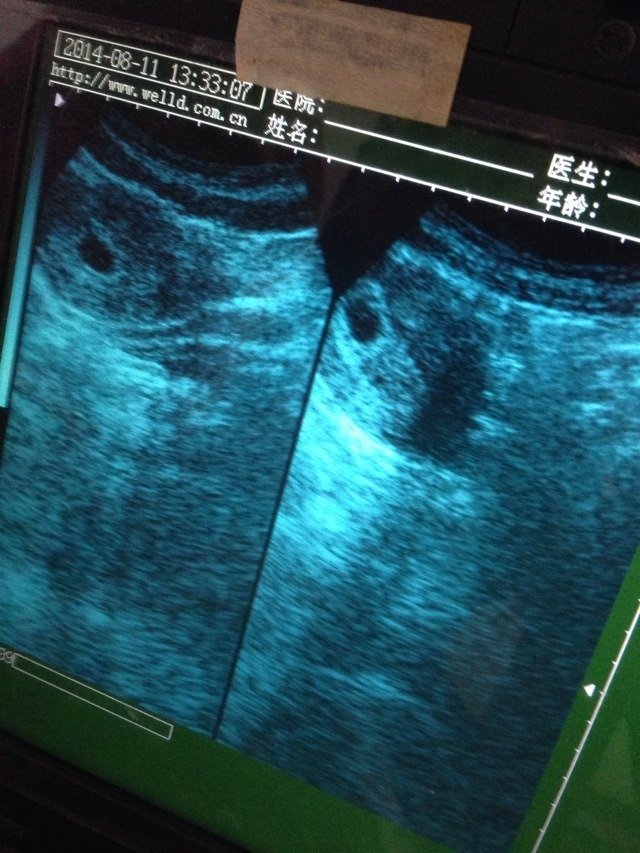

请问这个孩子到我肚子里有多久了 有图 请问这个孩子到我肚子里有多久了。有图 点击展开 失_Ca9R 2014-08-13 23:38 为您推荐: 其他回答 你好,这个图哪看得出多久呀,要用数据才能看呢,B超单上面都是会有如孕囊大小之类的数据的 有法律制裁你的 2014-08-14 16:44 这医生也无法看出来咯,医生也是根据单子上的数据说话的。 筱沛妈咪 2014-08-14 00:50 3个月 明鑫麻麻 2014-08-14 00:39 不是 151*****079 2014-08-14 00:08 要不你去大医院查查。 151*****079 2014-08-13 23:53 加载更多 相关问题 一岁小孩肚子身上有红点,有图,请问医生这是怎么回事? 我想问下,怀孕50天,宝宝掉了,做月子要做多久,这期间拉肚子会不会影响什么 我刚查出怀孕没多久,这两天有点拉肚子,有没有事呀?